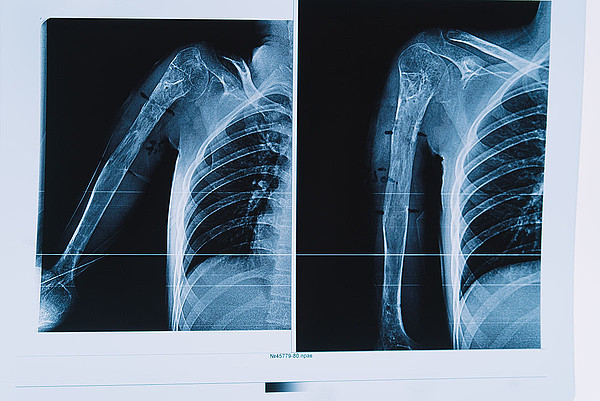

29112022-16.